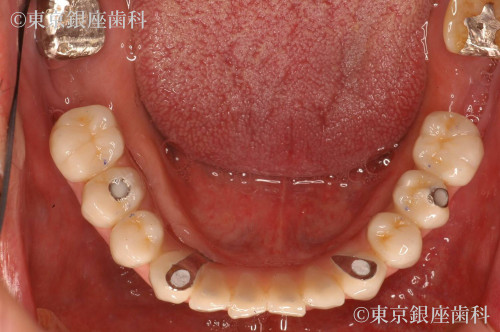

昔行ったインプラントからワンデイインプラントに変更

歯周病が進行したため、上下でワンデイインプラントを実施